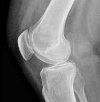

Рентгенография коленного сустава

Рентген коленного сустава. Метод лучевой диагностики применяется для оценки состояния коленного сустава. При травмах его назначают при подозрении на перелом мыщелков, мыщелков и бугристость большеберцовой кости, перелом головы и шеи малоберцовой кости, перелом и вывих надколенника. В других отраслях медицины он используется для лечения аномалий развития, опухолей, дистрофических дистрофических заболеваний и воспалительных заболеваний. Стандартное исследование проводится в двух проекциях (правой и боковой). Не требуется обучение Процедура не рекомендуется для детей и беременных женщин.

В травматологии рентгенограммы коленного сустава назначают при переломах бугристости и мыщелков большеберцовой кости, переломах шейки и головки малоберцовой кости, переломе мыщелка бедренной кости, вывихе и переломе бедренной кости. коленная чашечка. В ортопедии методика используется в процессе диагностики остеоартроза и аномалий развития. В ревматологии показаниями процедуры являются боль и отек колена при ревматоидном артрите и других заболеваниях. В онкологии исследование проводится при подозрении на злокачественную или доброкачественную опухоль дистального отдела бедра, проксимального отдела малоберцовой кости и большеберцовой кости.